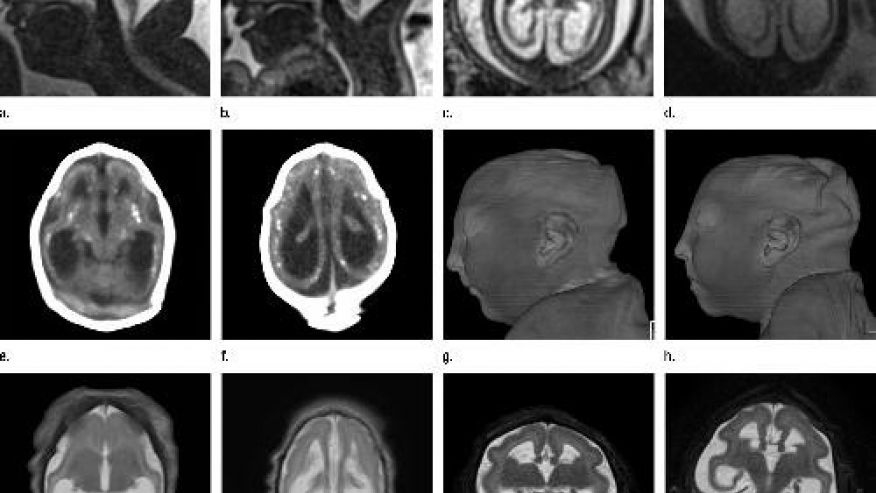

RT @FoxNews: New images detail how Zika attacks developing brains http://fxn.ws/2bSKNiB pic.twitter.com/I30JQJOJI4